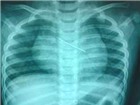

Chiếc kim ghim nằm chắn ngang trong lồng ngực của bé

Tại Nhi Đồng 1, sau khi khám và chụp phim X-quang ghi nhận dị vật hình một chiếc kim nhọn nằm trong ngực bệnh nhi. Ngay lập tức bác sĩ đã tiến hành nội soi thực quản tuy nhiên lần nội soi này không tìm thấy chiếc kim nên phải tiếp tục nội soi qua đường thở

Bác sĩ cho biết, ngay khi ống soi đi vào đường thở đã phát hiện nhiều vết trầy xước, khi soi đến cuống phổi bên phải mới phát hiện và gắp ra chiếc kim đang mắc tại đây. Sau khi lấy dị vật ra ngoài sức khỏe của bé cũng dần bình phục, tuy nhiên cháu phải điều trị bằng kháng sinh hỗ trợ phục hồi các vết xước do chiếc kim gây ra trong đường thở.